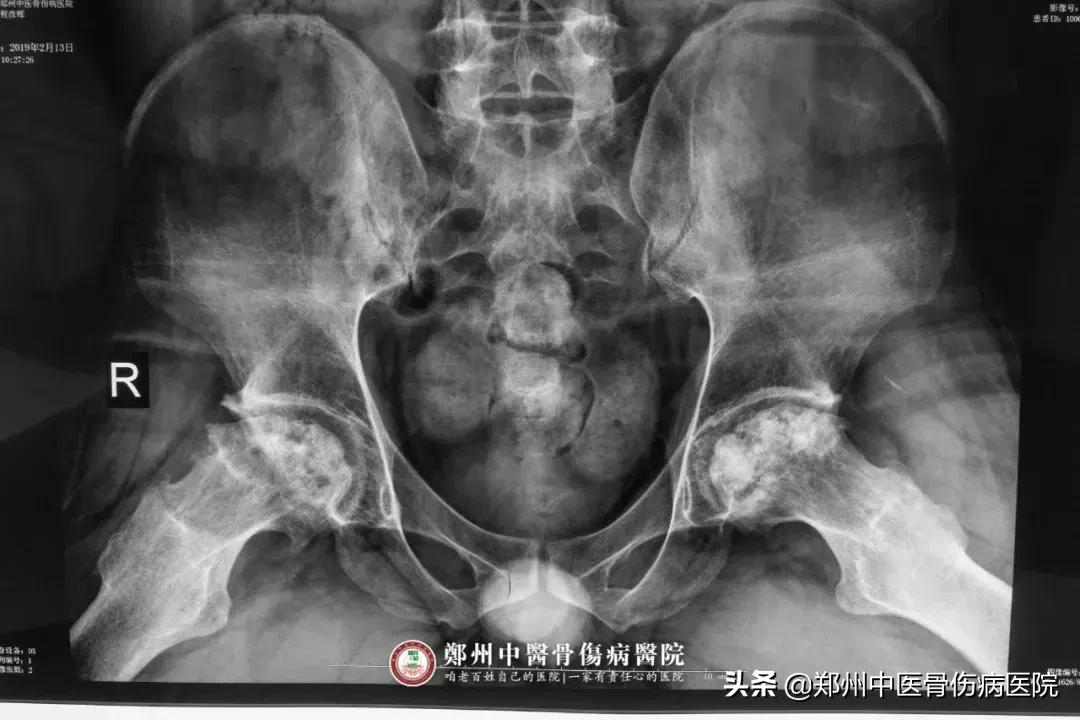

据了解,程先生无明显诱因出现双髋部疼痛,近5-6年来疼痛逐年加重,肌张力受到严重影响,走路十分困难,平时只能借助拐杖或轮椅行走。从此他就踏上了漫长的求医路,行走于各大知名医院,家里的药也是堆成了小山,钱是花了不少,但病情仍得不到控制。

就这样他半信半疑的来到了郑州中医骨伤病医院,经门诊详细检查,诊断为“骨性关节炎晚期”,收治于康复科。怎么会已经晚期了呢?!从那天开始他的心里就像压了一块大石头,怎么也开心不起来了。

入院后,康复科贺艳刚主任和管床大夫芦燕对他复杂的病情做了一个详细的诊治方案,通过医院的中医治疗如中频电、温针、药棒穴位按摩等,再配合康复运动、关节锻练及医院特制的中成药进行保守治疗,目的在于改善症状,缓解疼痛。六次住院治疗后,他的病情得到了很大改善,疼痛大大减轻。